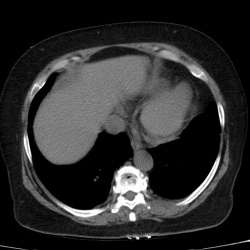

Мужчина 60 лет, находился на лечении в другой больнице около полу месяца назад по поводу острого панкреатита, из выписки - при поступлении рвота и боли в брюшной полости, делали УЗИ якобы без...